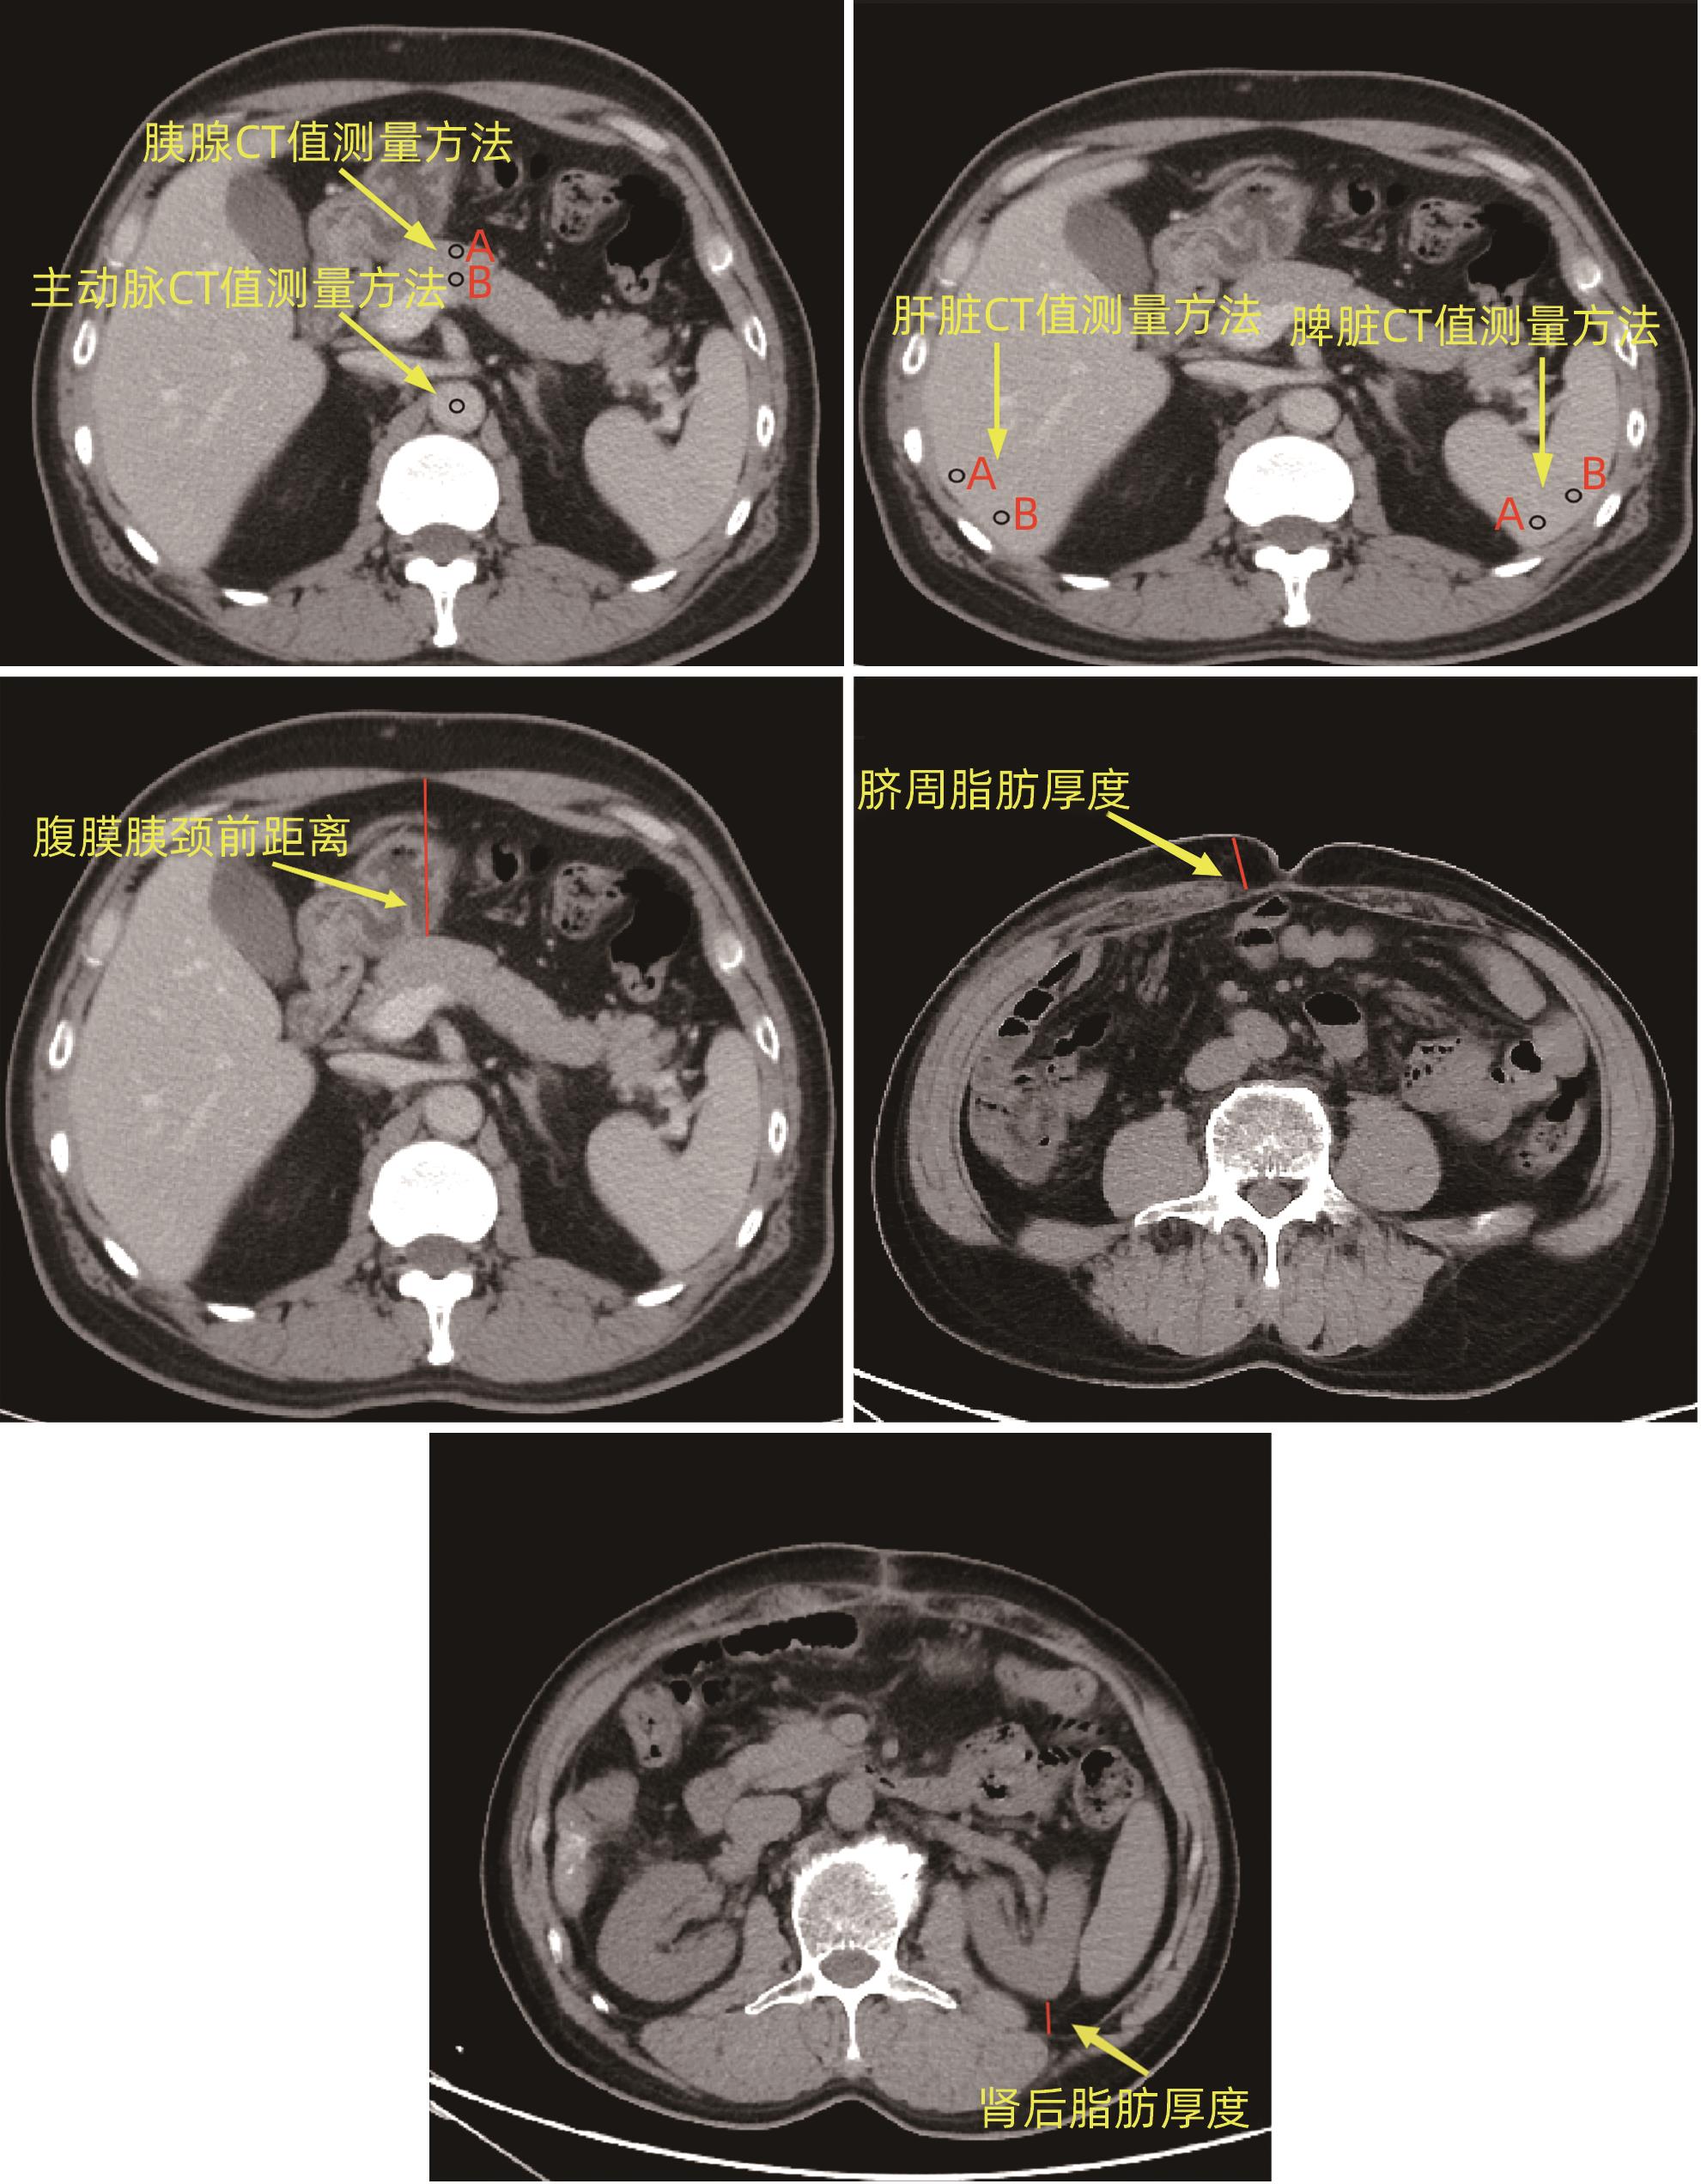

Value of preoperative alanine aminotransferase/aspartate aminotransferase combined with multi-phase CT radiological indicators in predicting clinically relevant pancreatic fistula after pancreaticoduodenectomy

Junhao PAN, Jian XIN, Chunhui WANG

2024, 40(9): 1859-1867. DOI: 10.12449/JCH240922

Abstract(880) HTML (364) PDF (2208KB)(55)

Abstract:

Objective  To investigate the risk factors for clinically relevant postoperative pancreatic fistula (CR-POPF) after pancreaticoduodenectomy (PD), and to establish a predictive model for early identification of CR-POPF.  Methods  A total of 244 patients who underwent PD in General Hospital of Northern Theater Command from January 2019 to October 2023 were collected, and based on strict inclusion and exclusion criteria, 179 patients were finally enrolled in this study. According to the presence or absence of CR-POPF, these patients were divided into non-CR-POPF group with 120 patients and CR-POPF group with 59 patients. Univariate and multivariate logistic regression analyses were used to determine the independent risk factors for CR-POPF, and a nomogram model was established based on such factors. The receiver operating characteristic (ROC) curve was used to assess the predictive performance of the model, the calibration curve was used to evaluate the calibration degree of the model, and the clinical decision curve and the clinical impact curve were used to analyze and validate the clinical application value of the model. The chi-square test or the Fisher’s exact test was used for comparison of categorical data between groups; the independent-samples t test was used for comparison of normally distributed continuous data between two groups, and the Mann-Whitney U test was used for comparison of continuous data with skewed distribution between two groups.  Results  Among the 179 patients, 59 (33.0%) developed CR-POPF. The multivariate Logistic regression analysis showed that alanine aminotransferase/aspartate aminotransferase (odds ratio [OR]=2.221, P=0.004), main pancreatic duct diameter (OR=0.276, P=0.022), the distance between the peritoneum and the anterior pancreatic neck (OR=1.034, P=0.027), and extracellular volume fraction (OR=0.001, P=0.005) were independent risk factors for CR-POPF. Based on the above four independent risk factors, a nomogram was established to predict CR-POPF after PD, with an area under the ROC curve of 0.837, a sensitivity of 0.932, and a specificity of 0.725. The decision curve and the clinical impact curve also showed that the nomogram had good clinical practicability.  Conclusion  Preoperative clinical indicators combined with multi-phase CT have a good performance in predicting CR-POPF after PD, which can be used to early identify patients at high risk of pancreatic fistula before surgery and provide further guidance for clinical work.